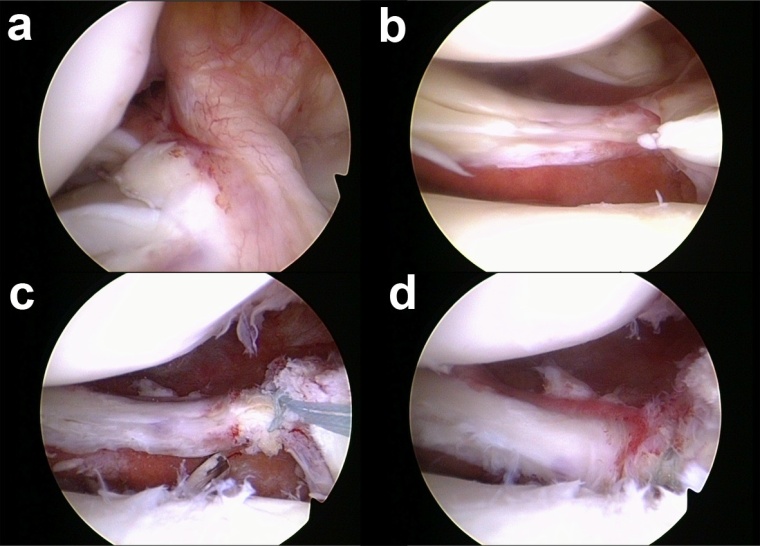

Aufgrund der schwerwiegenden Folgen dieser Verletzung und den nur unbefriedigenden Ergebnissen nach konservativer Therapie oder Meniskus-Teilresektion wird mittlerweile die arthroskopische Refixation der Meniskuswurzel mittels transtibialer Auszugsnaht (Abb. 1 und 2) oder mittels Fadenanker (Abb. 3) als Therapie der Wahl angesehen [13,19]. Das Ziel einer solchen Operation ist die Wiederherstellung der Ringspannung des Meniskus und somit die Normalisierung von Kontaktdruck und Kontaktfläche. In einer Studie von Kim et al. [10] wurde bei 58 Patienten mit Komplettruptur der Innenmeniskus-Hinterhornwurzel die Ergebnisse einer Meniskus-Teilresektion (n = 28) mit denen einer transtibialen Auszugsnaht (n = 30) verglichen. Nach einem durchschnittlichen Follow-up von 47 Monaten zeigten Patienten nach Wurzel-Refixation in allen untersuchten Parametern (Lysholm Score, IKDC Score, Kellgren-Lawrence Score, Gelenkspaltverschmälerung) ein signifikant besseres Ergebnis. Auch andere Autoren konnten gute bis sehr gute Ergebnisse bei den meisten Patienten nach Refixation der Innen- oder Außenmeniskuswurzel aufzeigen [1,3,12,17]. Kritisch muss jedoch angemerkt werden, dass v.a. bei degenerativ bedingten Rissen der Innenmeniskuswurzel die Heilungskapazität als eingeschränkt angesehen werden muss [23]. Als negative Prädiktoren konnten Moon et al. [17] eine Varusfehlstellung größer 5°, Knorpelschäden Grad 3 und 4 und das Ausmaß der präoperativen Meniskus-Extrusion identifizieren. Daher muss bei Patienten mit signifikanter Varus-Gonarthrose die Indikation zur Wurzelrefixation kritisch abgewägt werden, insbesondere vor dem Hintergrund, dass auch eine valgisierende Umstellungsosteotomie in diesem Patientengut eine probate Therapieoption zu sein scheint [18].

Abb. 2: Refixation der Außenmeniskus-Hinterhornwurzel mittels transtibialer Auszugsnaht.

(Kombinierte Verletzung aus VKB-Ruptur (a) und Komplexriss der Außenmeniskus-Hinterhornwurzel mit radiärer und longitudinaler Komponente (b). Nach Anschlingen der Außenmeniskus-Hinterhornwurzel wird ein transtibialer Bohrkanal angelegt (c) und die Fäden hierüber nach extraartikulär ausgeleitet (d).